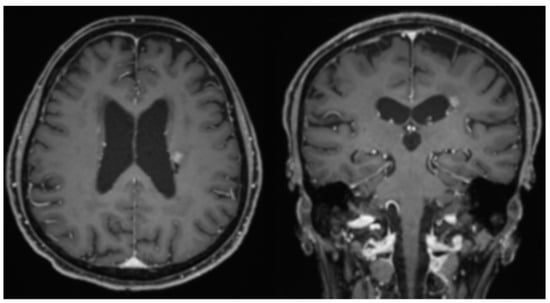

2. Case Report